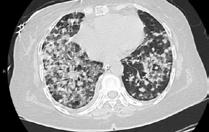

A 58-year-old female with recently diagnosed COVID-19 pneumonia was found to have a dry cough and dyspnoea in the setting of persistent bilateral hilar and mediastinal lymphadenopathy associated with bilateral nodular infiltrates. Of note, she immigrated to the USA from India 10 years prior, with the most recent travel to India 2 years ago. Quantiferon testing upon return to the USA was negative at that time. Workup included bronchoscopy with endobronchial ultrasound revealing non-caseating granulomas with negative stains for acid-fast bacilli (AFB). She was diagnosed with Stage 3 sarcoidosis and initiated on prolonged steroid taper with improvement of symptoms. With taper of steroid dose, however, she developed lymphocyte-predominant exudative effusion with negative cultures, and was reinitiated on a protracted steroid course with rapid symptom resolution. At 4-month follow-up, she had worsening CT findings upon steroid taper, and was started on azathioprine. One month later, she required hospital admission for worsening dyspnoea and fatigue. She was noted to be febrile, tachycardic, and tachypnoeic with worsening

hypoxia. Subsequent CT chest showed progression of bilateral nodular infiltrates with new right upper lobe consolidation and air bronchograms concerning for multifocal pneumonia (Figure 1). Incidentally, she was also noted to have calcified splenic granulomas. She developed rapid clinical deterioration, ultimately requiring mechanical ventilation, pressor support, and continuous renal replacement therapy. Repeat bronchoscopy revealed diffuse alveolar haemorrhage with multiple AFB smears positive for Mycobacterium tuberculosis. She was immediately initiated on quadruple therapy, but unfortunately, despite treatment, developed refractory shock and passed away 2 weeks after initial presentation.

A) Initial adenopathy with peripheral patchy ground glass opacities in the right lung following COVID-19 pneumonia. B) Persistent bulky adenopathy 1 year after initial presentation. C) Extensive nodularity throughout the right lung with increasing confluent opacities in the right upper lobe and stable mediastinal lymphadenopathy 2 years after initial presentation. D) Tuberculosis superimposed on sarcoidosis with progression of nodular infiltrates, worsening right upper lobe consolidation, and air bronchograms with incidental calcified splenic granulomas (not pictured).

Figure 1: CT progression of patient’s sarcoidosis and tuberculosis.